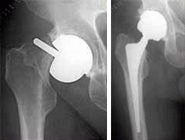

BHR /BMHR / Metal on metal large head diameter

Left: Birmingham Hip Resurfacing (BHR)

Middle: Birmingham Mid-Head-Resection (BMHR)

Right: Metal on metal large diameter prosthesis

These three types of prostheses are part of a modular system that can be adapted to the age and activity of the patient and to pathological changes in the joint. All three have the same high quality and wear resistant metal on metal bearings.